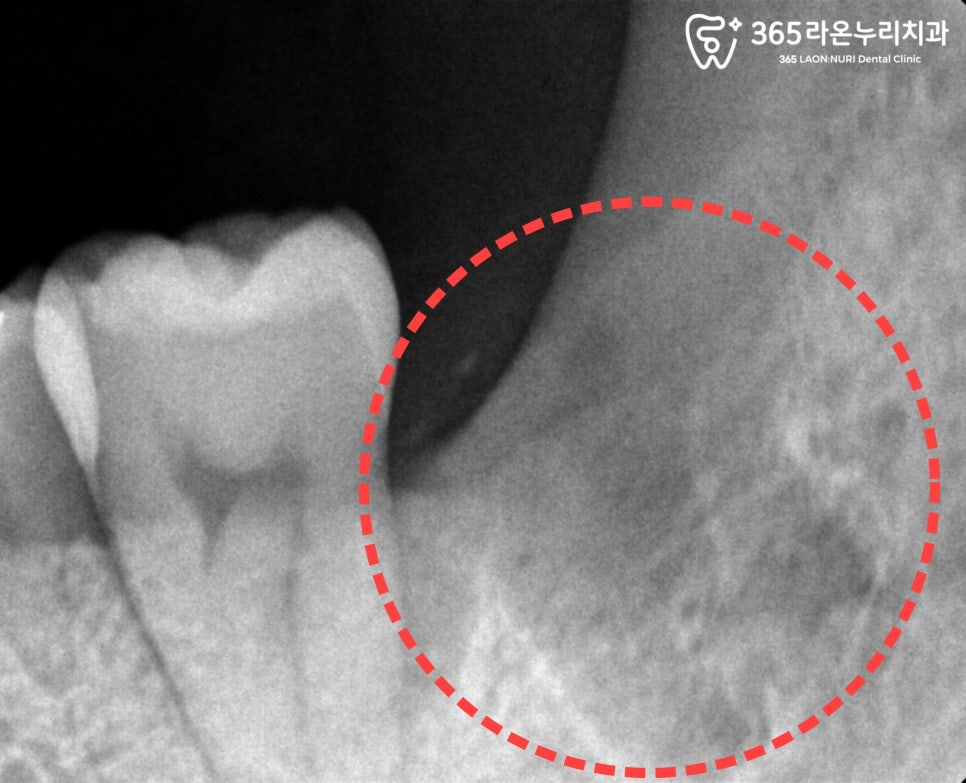

그런데 그 얇아진 잇몸 아래에는,

완전히 묻힌 매복치의 머리 부분이

바로 앞 치아 뿌리 근처에

위치해 있는 경우가 많습니다.

이 틈새로 들어간 세균이

염증을 일으키고,

시간이 지나면서

뼛속 깊은 조직까지 퍼지게 됩니다.

결국,

앞에 있는 어금니 뿌리 주변의 뼈가

녹아버리는 문제까지 생길 수 있습니다.